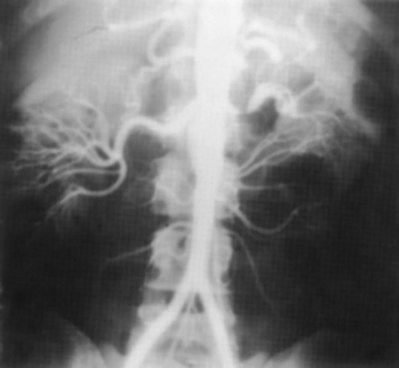

Since its introduction in the early 1970s, renal artery embolization (RAE) has been employed for palliation of inoperable renal tumors, to control bleeding, and as part of multimodal treatment of hypervascular metastatic disease (Almgard et al, 1973). In addition, RAE is used as a preoperative adjunct to resection of locally advanced renal tumors, with or without metastases (Paster et al, 1975) (Fig. 54–15).

Figure 54–15 A, Aortogram in a patient with a left hypervascular renal mass. Note the pooling of contrast medium in the upper pole. B, Left selective artery angiogram before coil placement. C, Aortogram after coil placement demonstrating abrupt cutoff of flow from the left renal artery.

Proposed benefits of preoperative RAE include shrinkage of an arterialized tumor thrombus to ease surgical removal, reduced blood loss, facilitation of dissection due to tissue plane edema, ability to ligate the renal vein before the renal artery at time of nephrectomy, and modulation of the immune response (Klimberg et al, 1985; Bakal et al, 1993; Kalman and Varenhorst, 1999; Schwartz et al, 2007; Wotkowicz and Libertino, 2007; Wszolek et al, 2008). Ligation of the renal vein before the renal artery is useful in the setting of hilar tumors, tumors with significant medial extension, or considerable perihilar adenopathy (Schwartz et al, 2007; Wotkowicz and Libertino, 2007; Wszolek et al, 2008). Before ligating the renal vein, one should characterize the completeness of embolization to prevent unnecessary blood loss in cases of incomplete embolization. In the senior author’s experience this assessment can be made by evaluating renal venous return during surgery. In addition, angioembolization can also be useful for renal tumors associated with large arteriovenous malformations that are having a deleterious hemodynamic impact (Figs. 54-16 and 54-17).

The data regarding preoperative RAE are limited, without any randomized trials evaluating the technique. As a result, in some institutions, surgeons rarely employ preoperative RAE (Boorjian et al, 2007). It is the practice of the senior author to perform preoperative RAE for large renal tumors with hypervascular characteristics or IVC tumor thrombus (Wotkowicz and Libertino, 2007). The ideal timing of nephrectomy after embolization is unclear (Craven et al, 1991; Weckermann et al, 1992; Kalman and Varenhorst, 1999; Schwartz et al, 2007). At the Lahey Clinic, surgery usually is timed 4 weeks after angioinfarction. An imaging study to assess the cranial limit of tumor thrombus is repeated shortly before the operation. Although prospective trials are needed to evaluate the role of preoperative RAE in the treatment of renal cell carcinoma, the senior author has found it a useful preoperative adjunct in the management of locally advanced RCC.